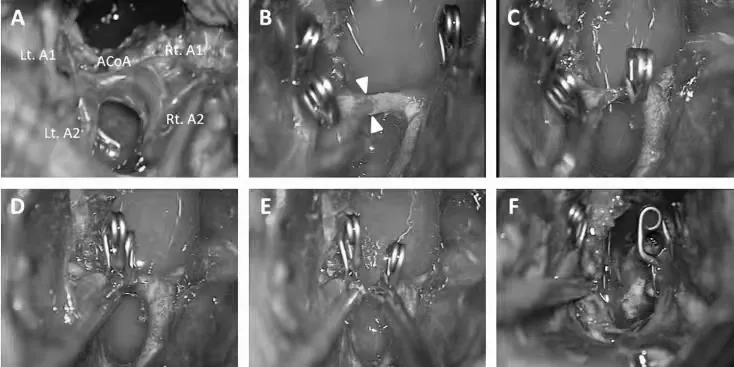

切除累及视交叉的肿瘤,于垂体下方识别垂体柄;

逐步暴露前交通动脉和终板;

打开终板进入第三脑室前方,实现充分瘤内减压;

暴露基底动脉分叉和P1段动脉,完整保留下丘脑及后循环血管;

前交通动脉意外撕裂,因无法修复,决定分离动脉并于两个A2段维持供血,夹闭并离断前交通动脉;

控制出血并保障血管通畅,实现残留肿瘤的顺利切除。